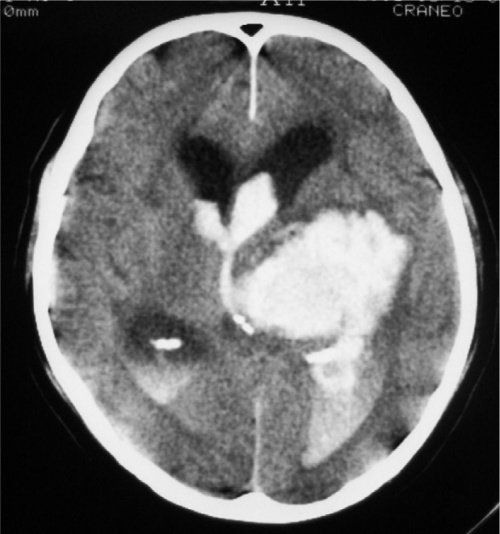

HEMORRAGIAS CEREBRALES

Las hemorragias cerebrales son una emergencia médica que ocurre cuando se produce un sangrado dentro del cerebro o en sus alrededores. Este tipo de hemorragia puede causar daños graves y permanentes, por lo que es crucial un diagnóstico y tratamiento rápidos.